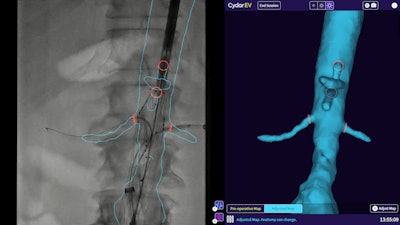

Featuring cloud-based artificial intelligence (AI) and computer-vision technology, EV Maps facilitates creation of a patient-specific 3D map of the target vasculature that surgeons can use to plan surgery, Philips said. The software then utilizes these maps to augment intraoperative live image guidance, updating the maps in real-time to account for deformations, such as guidewires and instruments that deform the patient's blood vessels.